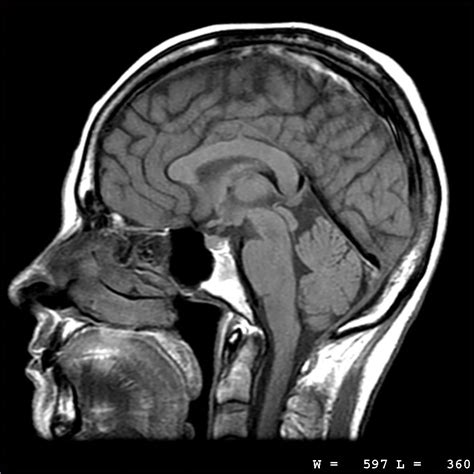

Hey guys! Today we’re diving deep into a really common issue that pops up in MRI scans: ripple artifacts . You know, those wavy, streaky lines that can sometimes mess up an otherwise perfectly good image? Yeah, those! It’s super important for us to understand what causes these pesky artifacts and, more importantly, how we can get rid of them or at least minimize their impact. Because let’s be real, when you’re trying to get clear diagnostic information, any kind of image degradation is a big no-no. We want those images to be as crisp and clean as possible, showing us exactly what we need to see without any visual noise. So, buckle up, because we’re going to break down the science behind ripple artifacts, explore the different types, and chat about some awesome techniques that radiologists and technologists use to combat them. Understanding these artifacts isn’t just for the pros, either. If you’re a patient who’s had MRIs, knowing about this stuff can help you understand why sometimes repeat scans are necessary or why an image might look a little ‘off’. It’s all about making the MRI experience smoother and the results more reliable for everyone involved. We’ll cover everything from the basic physics that lead to these artifacts to the practical steps taken during and after the scan to ensure diagnostic quality. So, whether you’re a student, a tech, a radiologist, or just plain curious, this guide is for you! Let’s get started on unraveling the mystery of MRI ripple artifacts and how we conquer them.

Alright, let’s get down to brass tacks. Ripple artifacts in MRI are essentially unwanted patterns that appear in the final image, disrupting the true signal from the patient’s tissues. Think of them as visual noise that can obscure important details. The primary culprit behind these artifacts is often related to subtle variations in the magnetic field. You see, MRI relies on incredibly precise magnetic fields to align the protons in your body. When these fields aren’t perfectly uniform, or when they fluctuate even slightly, it can lead to distortions in the data that gets collected. This is where the ‘ripple’ effect comes in. These tiny magnetic field imperfections cause the protons to precess (wobble) at slightly different frequencies, and this variation gets translated into signal loss or intensity changes in the image, manifesting as those characteristic wave-like patterns. It’s a bit like trying to listen to a radio station where the signal keeps fading in and out – you lose the clarity of the music. In MRI, we lose the clarity of the anatomical structures. Several factors can contribute to these magnetic field inhomogeneities. One major player is the gradient system itself. Gradient coils are responsible for spatially encoding the MRI signal, but if they aren’t perfectly manufactured or if they experience temperature fluctuations, they can introduce distortions. Another significant factor is the patient’s anatomy and the materials they might have inside them. Metal implants, for instance, are notorious for causing magnetic susceptibility artifacts, which can indirectly lead to or exacerbate ripple patterns. Even the RF coils used to transmit and receive the signal can contribute if they aren’t perfectly shielded or if there’s interference. The process of acquiring MRI data involves complex interplay between magnetic fields, radiofrequency pulses, and sophisticated electronics. Any hiccup in this chain can result in artifacts. It’s crucial to remember that MRI is an incredibly sensitive technique, and even minor deviations can have a noticeable impact on image quality. This sensitivity is what makes MRI so powerful, but it also makes it susceptible to these kinds of disruptions. We’re talking about imperfections measured in parts per million, which can still have a significant effect. So, when we talk about ripple artifacts, we’re really talking about the MRI scanner’s response to these subtle, but impactful, magnetic field variations and signal inconsistencies. It’s a delicate balance, and maintaining that balance is key to producing diagnostic-quality images. We strive for perfection, but in the real world, a little imperfection can creep in, and that’s where understanding these artifacts becomes paramount. We can’t always eliminate them entirely, but by understanding their origin, we can definitely manage them.